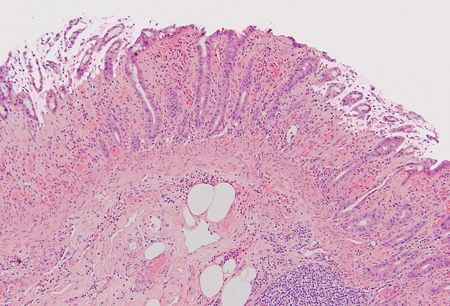

Colitis por isquemia

- Colitis infecciosa

- Colitis ulcerosa

- Enfermedad de Crohn